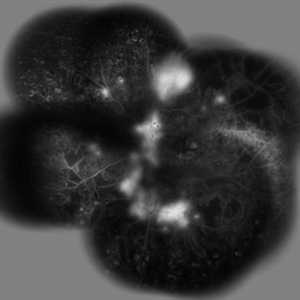

Behcet's Disease Behcet's DiseaseMar 13 2013 by Hamid Ahmadieh, MD Late phase FA of the right eye of a 23-year-old man with retinal vasculitis and branch retinal vein occlusion (BRVO) due to Behcet's disease . Photographer: Solmaz Shahmohammad, Negah Eye Center, Tehran Imaging device: Heidelberg Spectralis Condition/keywords: branch retinal vein occlusion (BRVO), retinal vasculitis

Behcet's Disease Behcet's DiseaseMar 13 2013 by Hamid Ahmadieh, MD Wide field FA of the right eye of a 23-year-old man with retinal vasculitis and branch retinal vein occlusion (BRVO) due to Behcet's disease . Photographer: Solmaz Shahmohammad, Negah Eye Center, Tehran Imaging device: Heidelberg Spectralis Condition/keywords: branch retinal vein occlusion (BRVO), retinal vasculitis